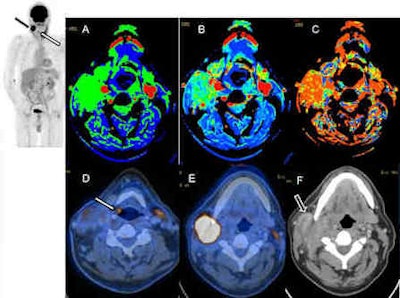

CT perfusion (CTP) performed in combined PET/CT scans can provide valuable extra information about tumor behavior, and may help to differentiate between head and neck tumors and inflammatory lesions, Swiss researchers have found.

"PET/CTP can be integrated into a routine, contrast-enhanced PET/CT protocol for staging in ENT [ear, nose, and throat] cancers without additional use of contrast media," noted lead author Dr. Patrick Veit-Haibach, from the department of medical imaging at University Hospital Zurich, in an article published online by European Radiology on 9 July. "CTP and PET parameters were not significantly correlated, and hence the additional CTP values can provide additional insights into tumor behavior and their glycolytic status. Metastatic lymph nodes have high CTP values and can be possibly differentiated from the primary tumor lesion."

Thirty-five patients had a head and neck cancer, the researchers discovered. All CTP data were statistically different between tumors, inflammatory lesions, healthy tissue, and metastatic lymph nodes; PET/CT data were in part significantly different. CTP and PET parameters were not significantly correlated.

In the Zurich study, which was partly supported by Bayer Healthcare, the mean blood flow for malignant lesions was 89.6 mL/100 mg/min and 68.6 mL/100 mg/min for inflammatory lesions. Since the blood flow for malignant lesions was comparable with other studies available in the literature, those values around 90 mL/100 mg/min (when evaluated with the same postprocessing software) might support the diagnosis of malignant rather than nonmalignant ENT lesions in questionable cases when the SUVmax does not clearly indicate malignancy, the authors wrote. However, they did not apply any further receiver operator characteristics (ROC) analysis because they thought the patient number for that is somehow limited, especially concerning inflammatory lesions.